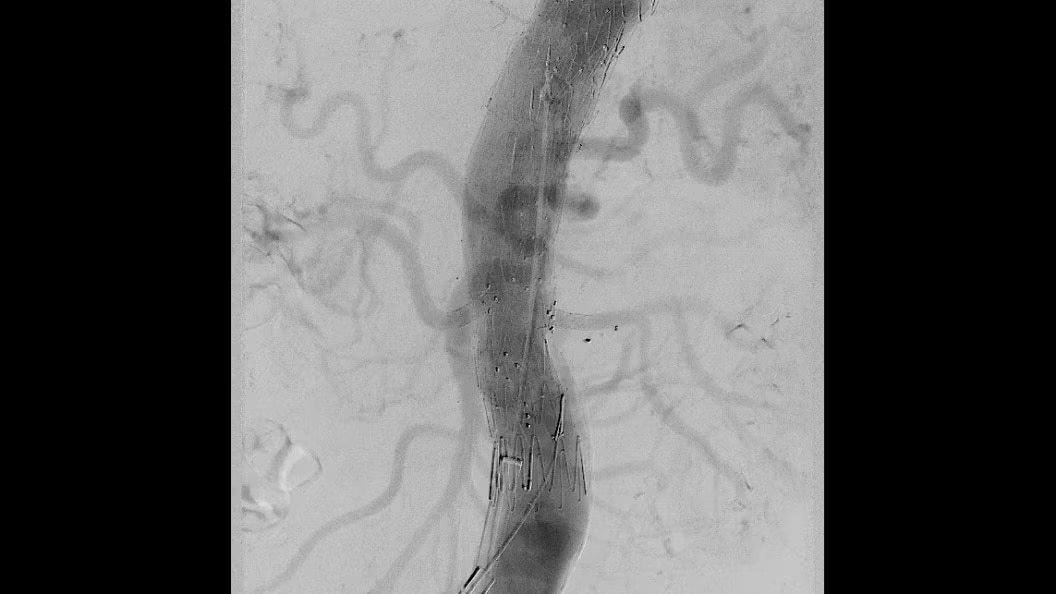

Advanced CBCT for accurate diagnostic and treatment planning

Experience the precision of cone-beam CT, offering high-resolution 3D imaging for accurate diagnostics and treatment planning with enhanced safety and efficiency.